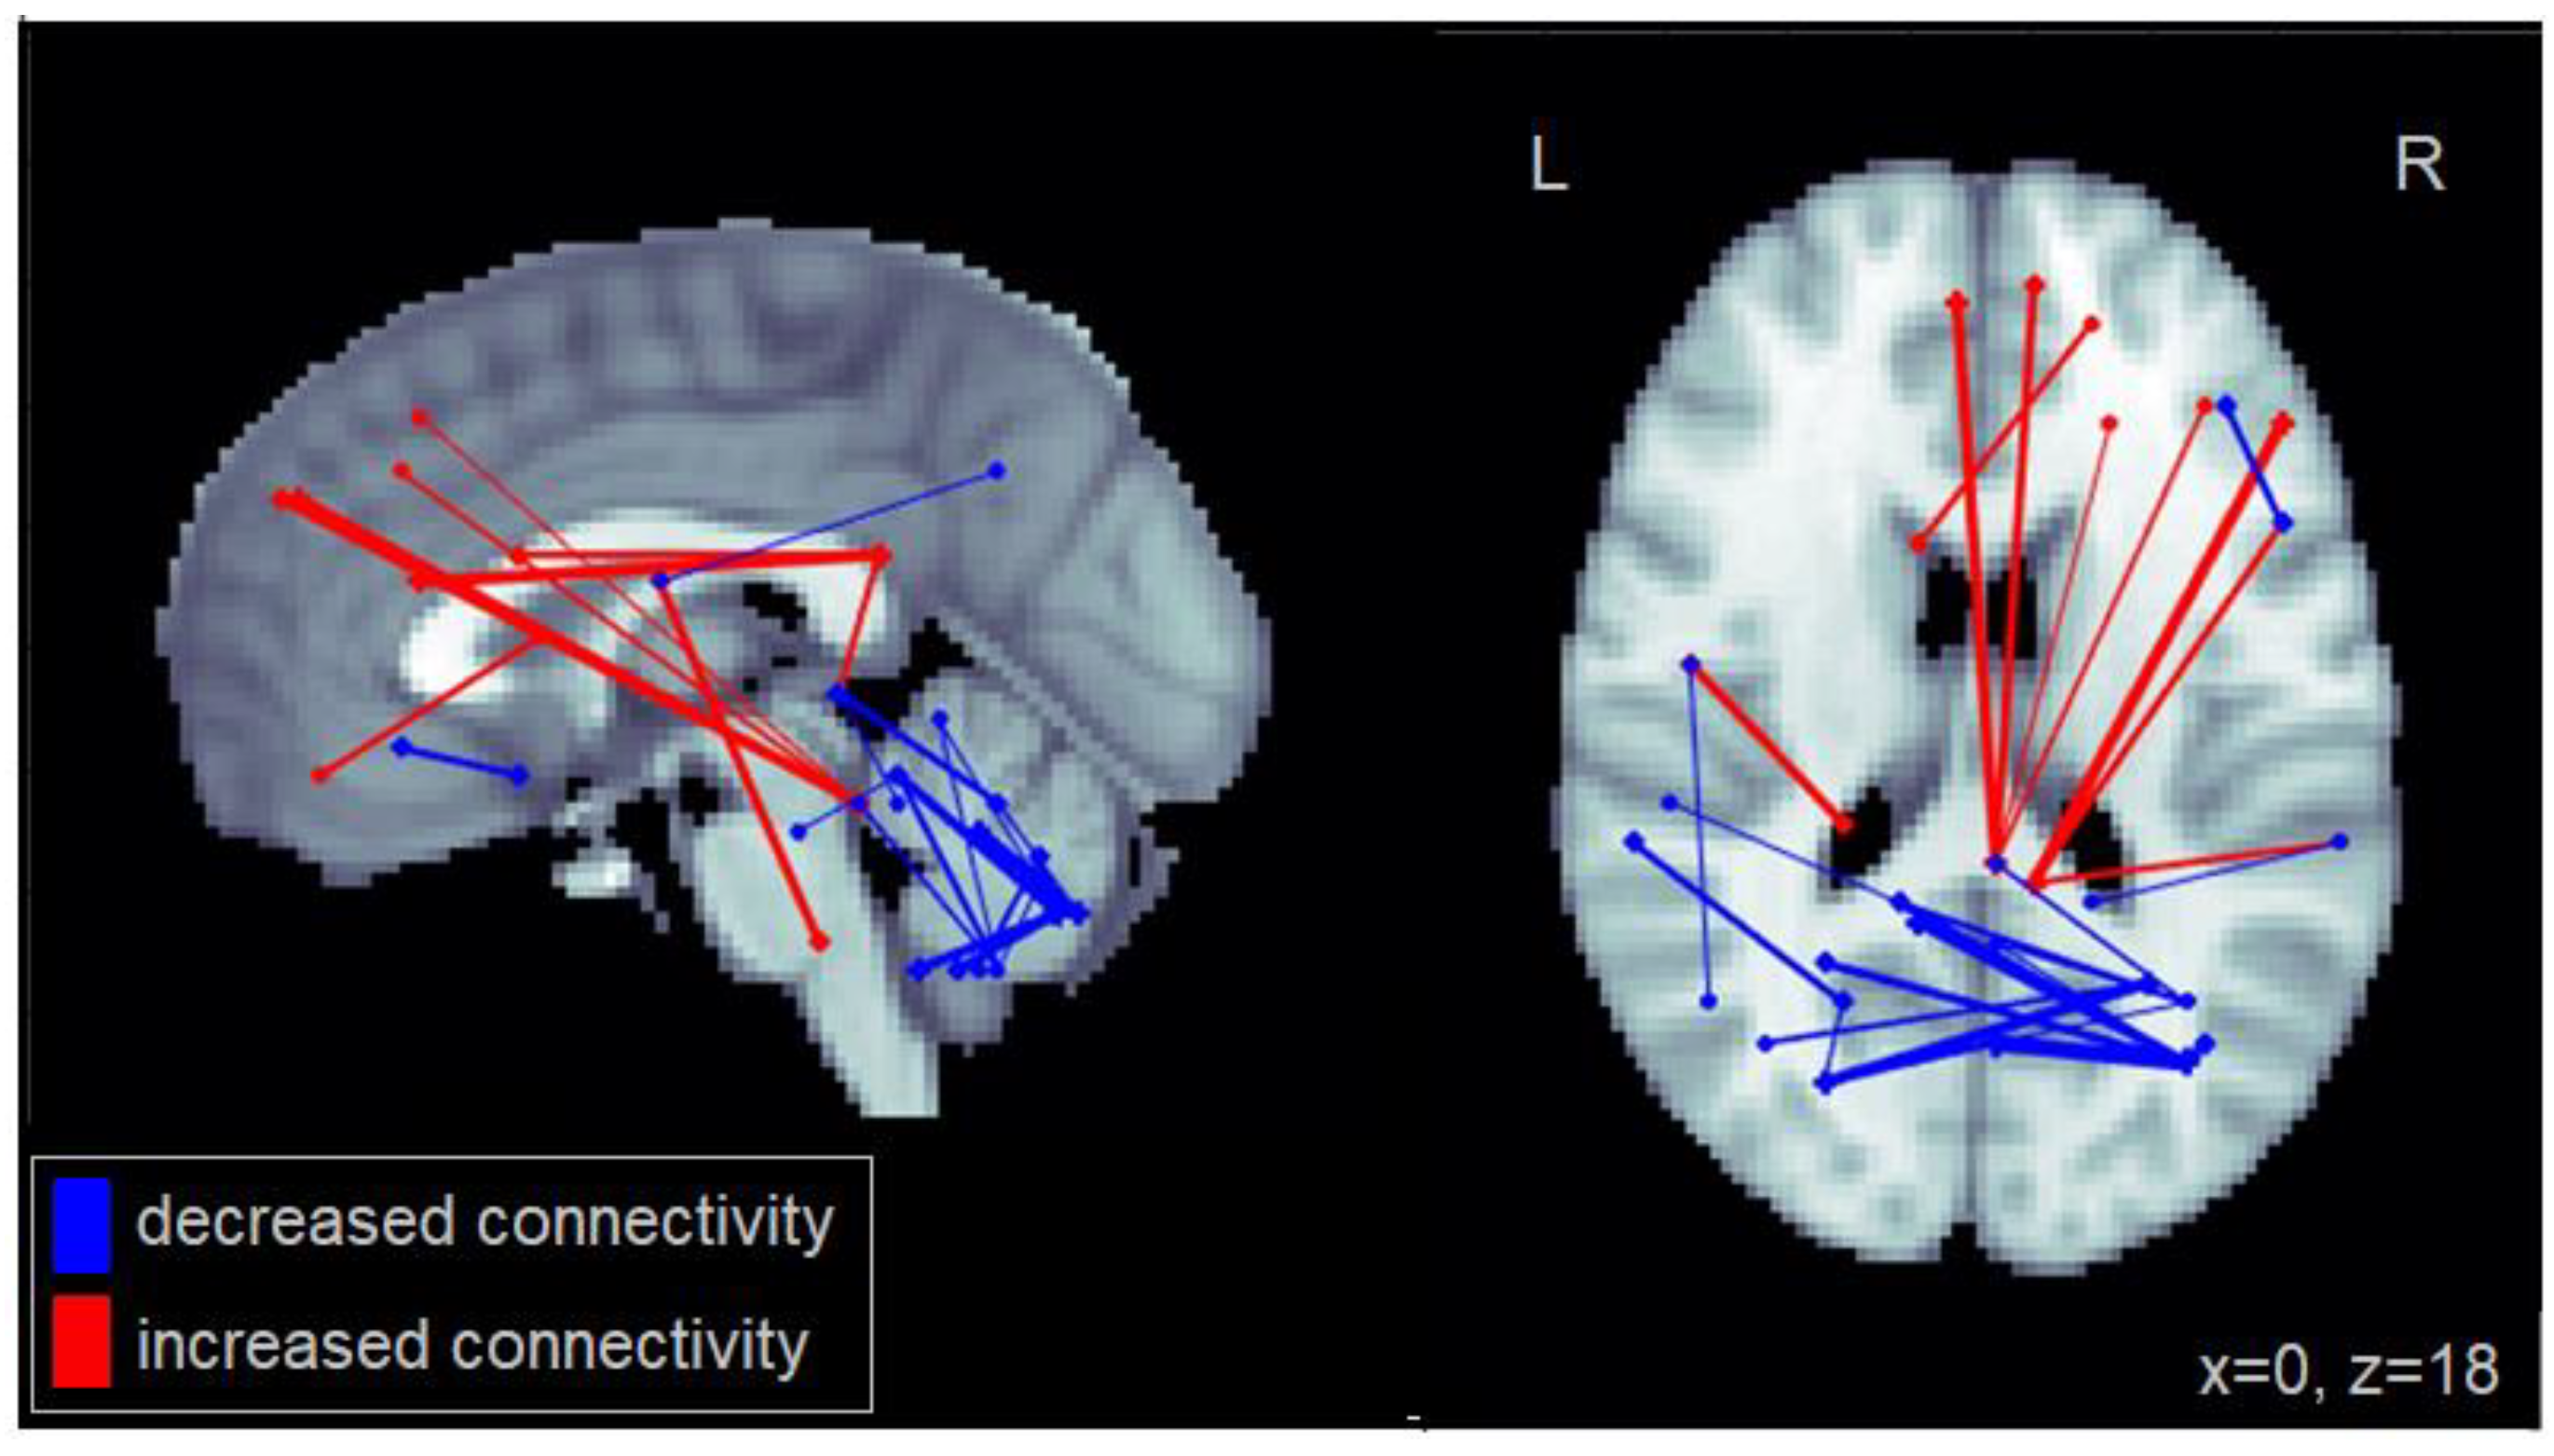

Compared to healthy controls, patients with MCI generally showed reduced functional connectivity, particularly long-distance connections between frontal and posterior cortical regions (Figure 1). Specifically, the MCI group exhibited reduced connectivity between the middle frontal cortex and the superior and inferior parietal cortex; between the superior medial frontal cortex and the superior occipital cortex and the angular gyrus; and between the inferior frontal gyrus and the cuneus as well as the superior occipital cortex. Reduced connectivity was also observed between the inferior orbitofrontal cortex and the cerebellum, within the cerebellum, and between the caudate and the cuneus. The complete set of regions showing reduced connectivity among patients with MCI is reported in Table A1.

Figure 1.

Altered functional connectivity observed for the MCI group compared to the healthy control group. Blue lines denote functional connections with reduced connectivity in MCI patients, red lines denote increased connectivity (significant at FDR = 0.05). Connections are shown as projections in the sagittal and axial plane, with MNI anatomical underlays (slices at x = 0 and z = 18 respectively).